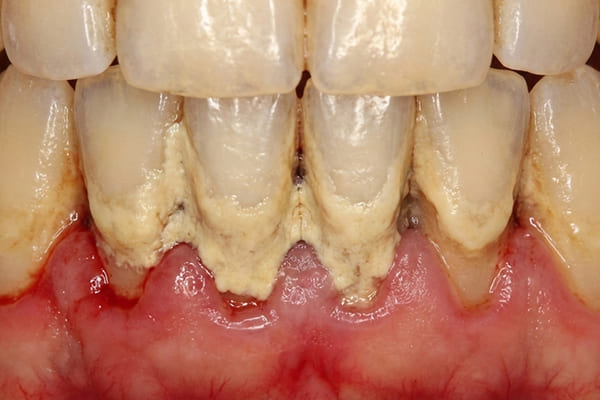

軽度歯周炎 危険度★★

軽度の歯周炎は歯茎が少し赤みを帯び腫れた状態になります。

軽度歯周炎の場合の目安は歯周ポケットが3~4mm程度と言われています。

この段階での治療法は、プラークや歯垢をスケーリングなどで取り除き、正しいブラッシングを毎日することです。

中度歯周炎 危険度★★★

中程度の歯周炎になると、口臭がおこり、歯茎が化膿します。ブラッシングをした際に膿がでることもあります。

歯周ポケットは4~5mm程度です。

この段階での治療法はスケーリングなどを使用して治療をしますが、歯周ポケットが5

mm以上深くなるとフラップ手術をする場合があります。フラップ手術は局所麻酔後、歯茎を切開し、隠れているプラークや歯石を取り除き、歯周病の進行を止める手術を行うことがあります。

重度歯周炎 危険度★★★★★

重度の歯周炎になると、歯がグラグラして、歯と接している歯茎がさらに腫れ、化膿が進みます。歯と歯の間が広がり、歯茎が下がって、歯が長く見えます。

この段階の治療法は再生療法を用いて歯周組織の再生をはかることが多いです。しかし、ここまで進行すると抜歯になる可能性が高くなります。